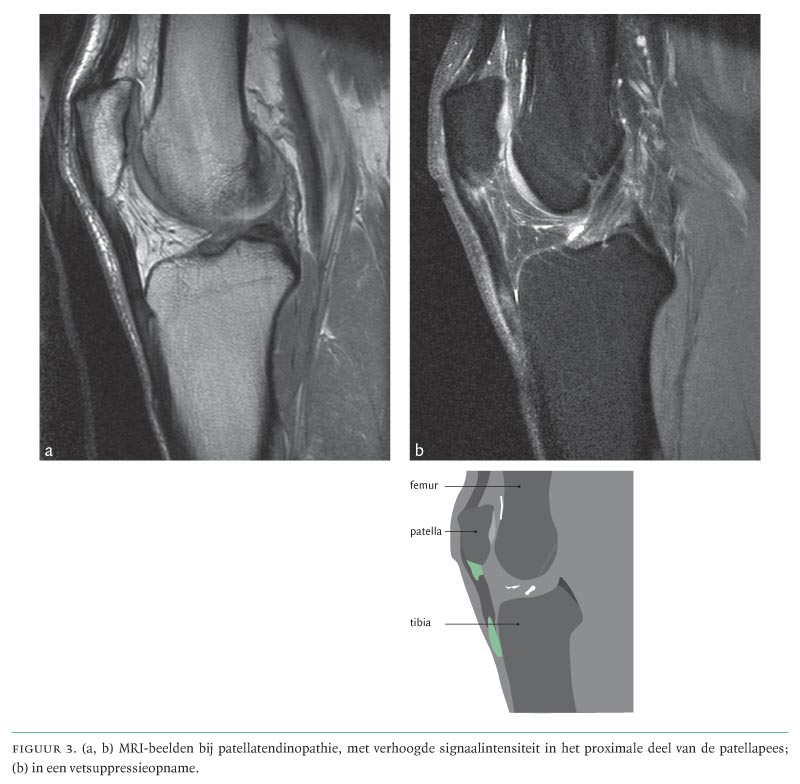

From www.ntvg.nl

Patellatendinopathie ('jumper's knee'); een veelvoorkomende en lastig te behandelen Jumper's Knee Radiology To determine the histopathologic findings of patellar tendinosis (jumper's knee) demonstrated with. The defining characteristics of pfps include knee pain, typically in an anterior distribution without radiation, as well as pain with flexion of the. Diagnosis is primarily made clinically with tenderness to. Studies dating back 40 years describe jumper's knee as a degenerative condition. Jumper's knee or patellar tendinosis. Jumper's Knee Radiology.